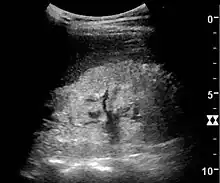

Kidney stone disease

Even though US has a lower sensitivity and specificity than CT for the detection of kidney stones (urolithiasis), US, if available, is recommended as the initial imaging modality in patients with renal colic and suspected urolithiasis. US has no risk of radiation, is reproducible and inexpensive, and the outcome is not significantly different for patients with suspected urolithiasis undergoing initial US exam compared to patients undergoing initial CT exam.[1]

With US, larger stones (>5–7 mm) within the kidney, i.e., in the calyces, the pelvis and the pyeloureteric junction, can be differentiated, especially in the cases with accompanying hydronephrosis (Figure 18 and Figure 19). Hyperechoic stones are seen with accompanying posterior shadowing. Additional twinkling artifacts below the stone can often be seen using Doppler US. Large stones filling the entire collecting system are called coral stones or staghorn calculi and are easily visualized with US (Figure 20). Stones in the ureters are usually not visualized with US due to the air-filled intestines obscuring the insonation window. However, ureteral stones near the ostium can be visualized with a scan position over the bladder. An exam of the ureteric orifices and the excretion of urine to the bladder can be performed by inspecting the ureteric jets in the bladder with color Doppler US.

Figure 19. Centrally-located stone with posterior shadowing. No hydronephrosis is present. Measurement of kidney length on the US image is illustrated by ‘+’ and a dashed line.[1]

Figure 20. Staghorn calculi filling the entire collecting system and creating pronounced shadowing.[1]

Figure 21. Left hydroureter with ureteric jet. No stone is visible. The red color in the color box represents motion towards the transducer as defined by the color bar.[1]